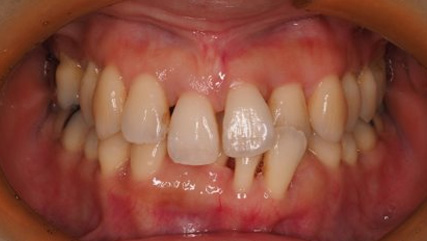

上顎前突といわれ、上顎の前歯が唇側に出ている状態を言います。

前歯が出ることで見た目の問題もありますが、口を閉じることができない、口呼吸をしてしまう、外傷などのリスクがあります。

日本人に叢生の次に多い不正咬合と言われており、自然に治ることはありません。また上の前歯が出ている事だけが気になるかもしれませんが、多くの場合、上顎の奥歯の位置に問題があることが多く、部分矯正でなく根本的な治療をした方がいい場合が殆どです。

口を閉じることができないことで、鼻呼吸でなく口呼吸をしてしまい、結果、成長期の場合顎の骨の成長を邪魔してしまうとも言われております。その他、口呼吸はアトピーなどを含むアレルギー症状の悪化、風邪を含むウイルス性の感染症にかかりやすいなどのリスクも増大してしまいます。

歯並びだけでなく全身への影響も多い為、早期の治療をおすすめ致します。

治療前

治療終了前